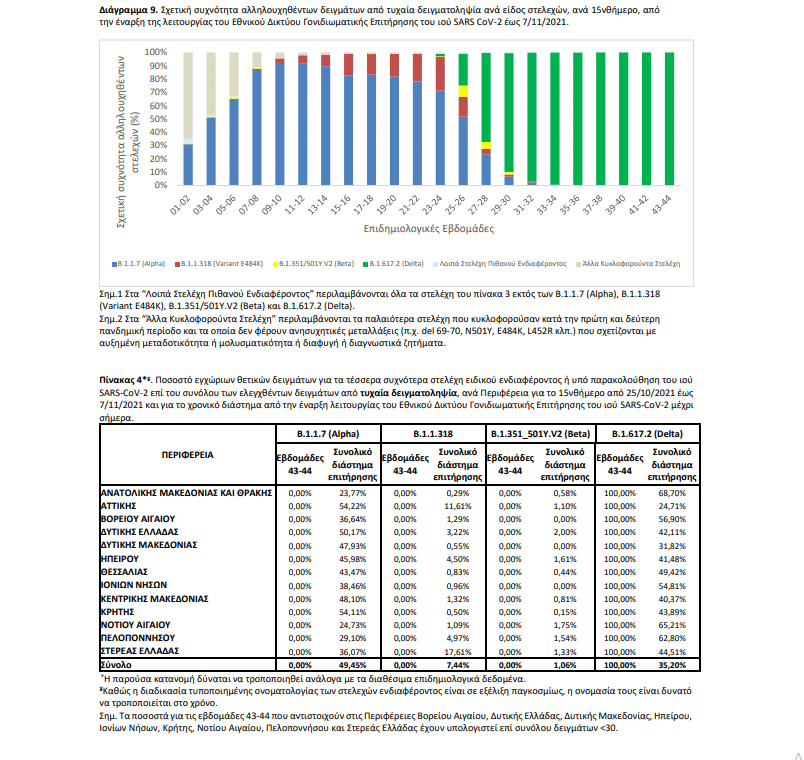

Από την έναρξη λειτουργίας του Εθνικού Δικτύου Γονιδιωματικής Επιτήρησης του ιού SARS-CoV-2 μέχρι σήμερα έχουν ελεγχθεί στην επικράτεια συνολικά 35.648 δείγματα από εγχώρια κρούσματα. Εξ αυτών 31.473 προέρχονται από τυχαία επιλογή δειγμάτων, 3.434 προέρχονται από στοχευμένη λήψη ή επιλογή δειγμάτων και για 741 δείγματα δεν είναι διαθέσιμος ο τρόπος επιλογής. Μεταξύ των 31.473 τυχαία επιλεγμένων δειγμάτων στην επικράτεια, τα τέσσερα πιο συχνά στελέχη ειδικού ενδιαφέροντος ή υπό παρακολούθηση που έχουν απομονωθεί είναι το Alpha, με ποσοστό 49,45%, ακολουθούμενο από το Delta με ποσοστό 35,20%, το B.1.1.318 (Variant E484K) με ποσοστό 7,44%, και το Beta με ποσοστό 1,06% (Πίνακας 4).

Η διαχρονική εξέλιξη της σχετικής συχνότητας των αλληλουχηθέντων δειγμάτων από τυχαία δειγματοληψία ανά είδος στελεχών, μέχρι και την εβδομάδα 44 απεικονίζεται στο Διάγραμμα 9. Από τα 3.434 δείγματα που έχουν ληφθεί ή επιλεγεί στοχευμένα, έχουν βρεθεί 3.270 στελέχη ειδικού ενδιαφέροντος ή υπό παρακολούθηση.